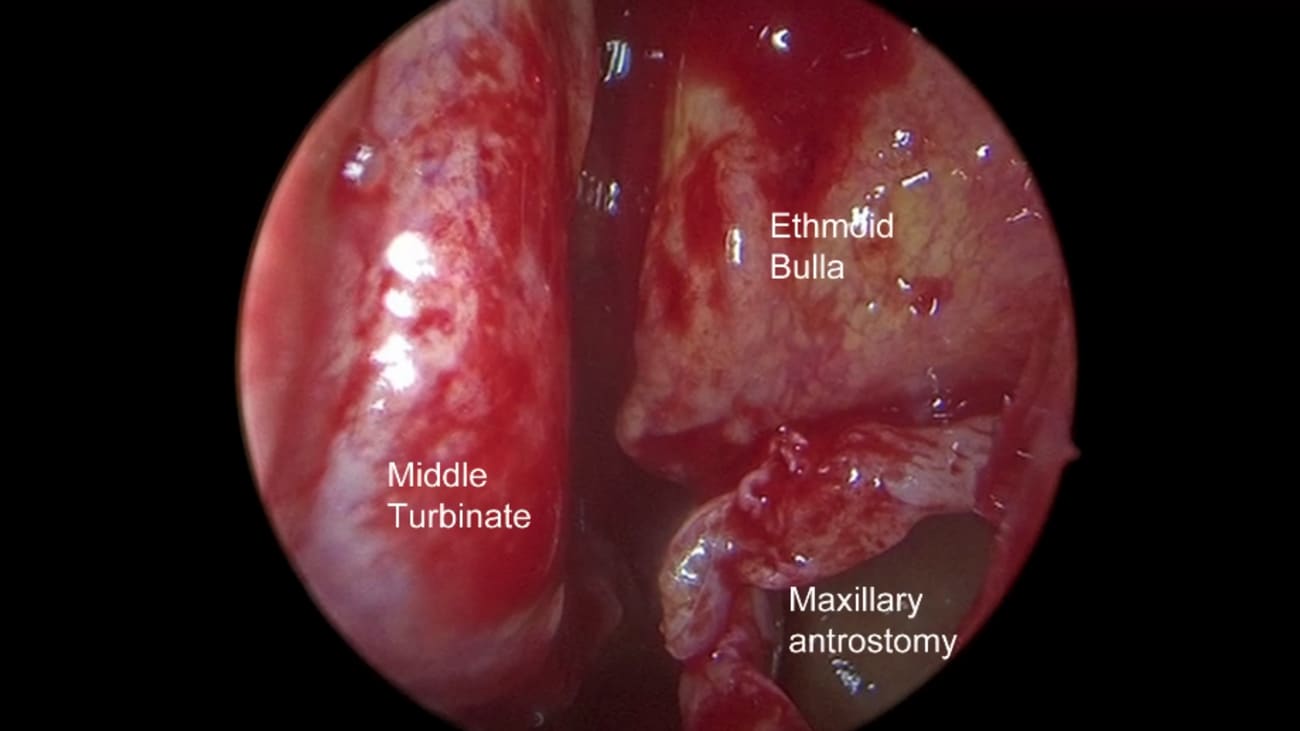

Mount Sinai sinus surgeons specialize in minimally invasive, functional endoscopic sinus surgery (FESS) for patients with chronic rhinosinusitis and sinusitis with or without nasal polyps. Sinus surgery for inflammatory disease allows medications such as nasal steroids, saline irrigations, and antihistamines to better reach their target areas. Polyp removal may also improve nasal congestion and nasal obstruction. This procedure is commonly performed along with septoplasty and inferior turbinate reduction to further open the nasal airways to improve breathing through the nose. Not all sinuses must be opened in order for surgery to be effective; surgeons will open a combination of the following sinuses: maxillary, ethmoid, frontal, and sphenoid on one or both sides. The extent of surgery is dependent on symptoms, anatomy, and the results of a CT scan. Sinus surgery is very effective in well-selected patients.